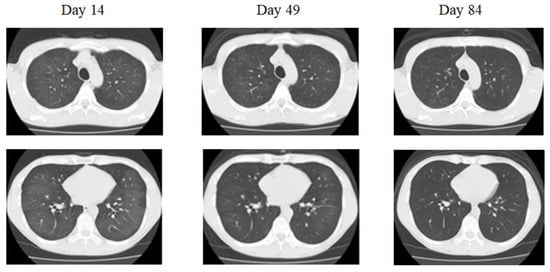

The initial findings were as follows: blood pressure: 125/83 mm Hg, pulse: 90 beats/min, body temperature: 36.1 °C, oxygen saturation (SpO2): 97% in room air, no cyanosis, clear respiratory sounds, and no obvious dry or moist rales, heart murmur, or edema of the extremities. Blood analyses conducted upon admission revealed that the patient’s complete blood counts, liver function, renal function, electrolytes, and CRP levels were within normal limits, except for the elevated levels of lactate dehydrogenase (LDH; 667 IU/L, normal range: 275–512 IU/L). The serum Krebs von den Lungen (KL)-6 level was 390 U/mL (normal range: <500 U/mL). The percentage of macrophages in bronchoalveolar lavage fluid (BALF) (Day 21) was 97.0%. Chest X-ray and chest computed tomography (CT) performed upon arrival revealed that diffuse ground-glass appearances in both lung fields and peripheral areas were absent (Figure 1).

He had a 28-pack-year history of cigarette smoking for 28 years. He did not take steroids. The light cough persisted and the chest CT performed approximately two months after the onset revealed a residual ground-glass appearance (Figure 1). Finally, three months later, the ground-glass appearance had cleared on the chest CT (Figure 1).

Figure 1. Chest X-ray and chest computed tomography (CT) in case 1. Bilateral diffuse, ground-glass opacity can be observed, but no pleural nadir shadow. A mosaic pattern can be observed in some areas (Day 14). There is a trend toward shadow reduction in both the upper and lower lung fields, but shadows are still present (Day 49). Improved completely (Day 84).